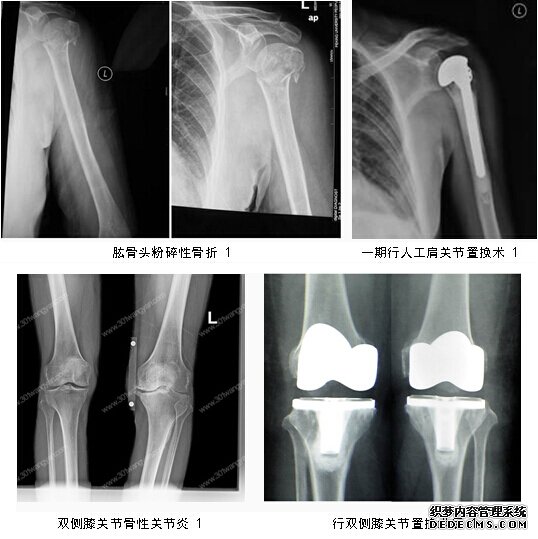

1、關節置換:我科近期成功開展了肩關節置換術、膝關節置換術及髖關節假體松動翻修術,極大的解除了患者的痛苦,該類手術的開展,標志著我科在關節置換方面上了一個新的臺階。達到了地區領先水平。

二、創傷學組:我科在四肢常見骨折的治療方面積累了豐富的臨床經驗。成功開展了微創小切口下人工髖關節置換術,有限內固定結合外固定支架治療復雜的開放性骨折,前后路固定復雜的骨盆骨折等新的業務,取得了良好的社會及經濟效益。

骨一科以關節、骨盆、下肢和小兒骨科為特色,較早開展了骨盆髖臼骨折的重建手術,肢體延長手術,小兒先天性髖臼脫位及成人下肢各種畸形的矯形術,關節周圍骨折的微創手術。2008年獲得天津薊州省人工關節置換準入并率先在天津薊州市展開人工關節置換手術。雙側股骨頭缺血壞死同期雙側髖關節置換術和關節鏡下膝關節疾病的微創手術區域領先水平。

2、對各類骨折創傷療效顯著,患肢功能恢復佳:特別是高齡股骨頸、轉子間骨折患者行人工關節置換治療;高齡轉子間骨折患者行PFN/PFNA治療;對嚴重暴力所致的復雜性骨盆骨折行髖臼重建+外固定架治療;對于股骨髁上粉碎性骨折行關節面重建+鎖定鈦板內固定治療;對于脛骨平臺骨折內固定聯合關節鏡下關節面復位治療;嚴重踝關節骨折如pillion骨折行內外側鈦板固定聯合關節鏡下關節面復位;對于開放性骨折行多平面外固定架及Ilizarov環形架治療;部分肢體毀損傷及骨、皮膚缺損行血管神經吻合及各種皮瓣修復治療;